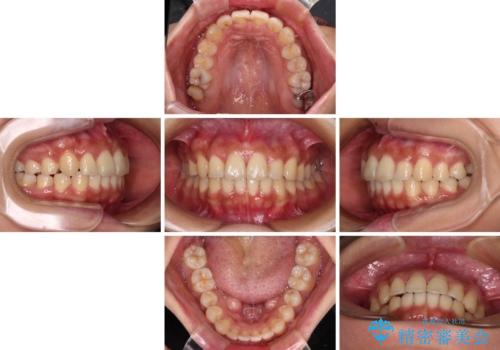

【モニター】歯列が狭くデコボコが気になる 急速拡大装置を用いたインビザライン矯正

- 患者様

- 30代女性

- 奥歯の咬み合わせと治療を放置したまま奥歯を気にして来院された患者様です。

上顎骨の幅が下顎骨よりも小さいので、拡大装置により骨幅を広げて上下関係を改善し、その後インビザラインにて歯並びを整えることとしました。

矯正治療後には土台のままとなっている歯をセラミッククラウンにて補綴治療を行うこととしました。